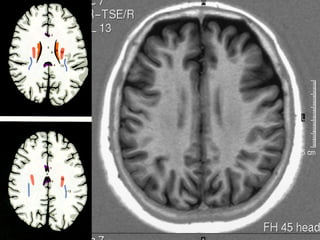

SISTEMA LÍMBICO

Amigdala

Hipocampo

Fórnix

Giro cíngulo

posterior

anterior